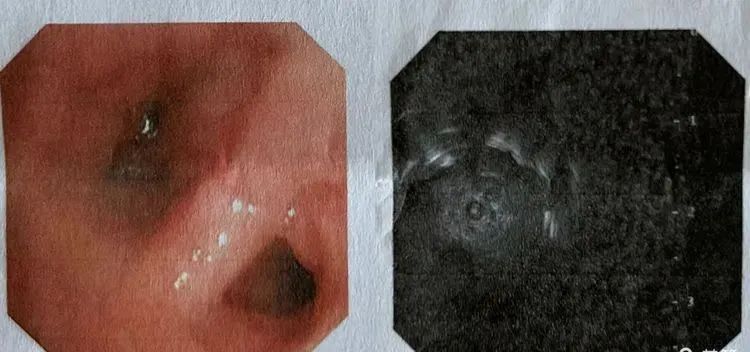

超细支气管镜

联合超声支气管镜小探头,

将外周不可见病变

转为可见病变!

我们在细镜观察下,

将超声小探头送到目标支气管探查,

探查到病变后,

再进行灌洗,刷检,活检!

细镜联合超声小探头减少出血,

真正做到了

精准、高效和安全。